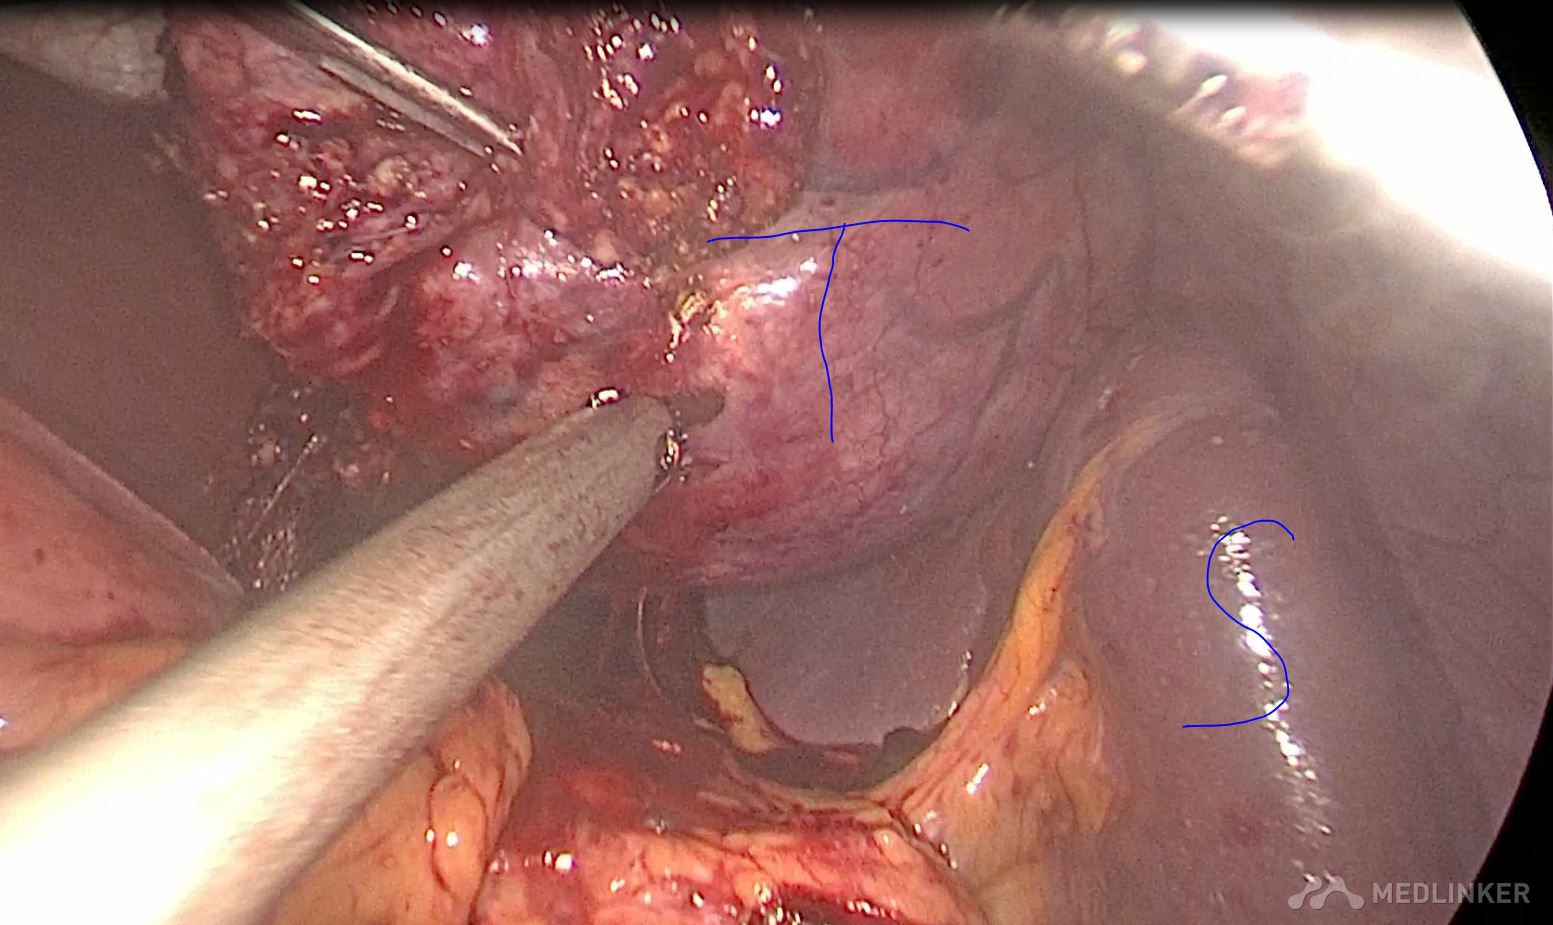

诊断 胰腺囊性肿瘤 囊腺瘤可能性大,术后病理 粘液性囊腺瘤 治疗 全麻下腹腔镜保脾胰体尾切除

术后恢复顺利,没有出现胰瘘。 胰腺粘液性囊腺瘤由于可能恶变,应该早期手术治疗,传统方式一般开腹手术,由于胰体尾与脾脏灌洗密切,经常需要联合脾脏切除。而脾脏除了具有免疫功能,还有滤血,毁血,储血等功能,故保留脾脏对于患者来讲意义肿大。腹腔镜手术由于独特视角以及放大作用,可以做到保脾胰体尾手术,术中尽量保留脾血管(Kimura手术),如果各种原因,脾血管无法保留,此时仍然可以尝试保脾(Warshaw手术),这时脾脏通过胃血管供血,术后功能良好。